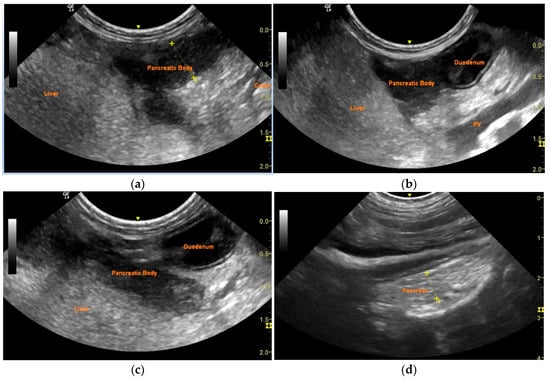

Successful Management of a Pancreatic Abscess in a Dog with Juvenile Diabetes Mellitus Through Ultrasound-Guided Drainage and Medical Therapy

2. Case Description